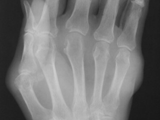

Psoriasis-Foot

Psoriasis-Foot